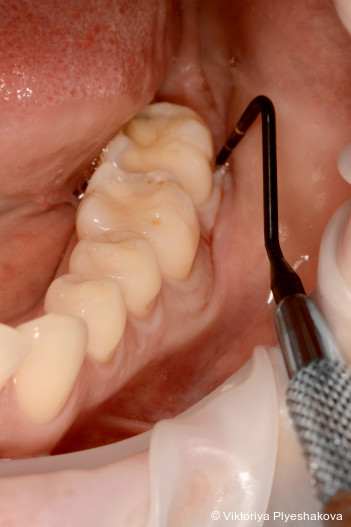

Vor der Instrumentierung wird ein Reinigungsgel aus Aminosäure-gepuffertem Natriumhypochlorit in die Tasche eingebracht. Dieses bewirkt eine deutliche Reduktion der Bakterienpopulation und erleichtert sowohl die Entfernung von Biofilm als auch von infiziertem Granulationsgewebe. Nach der Instrumentierung wird vernetzte Hyaluronsäure eingebracht, um die Gewebereparatur zu fördern, die Heilung zu beschleunigen und so einen Schutz vor erneuter bakterieller Invasion der behandelten Stelle zu verhindern.

Eine gründliche subgingivale Instrumentierung stellt einen entscheidenden Schritt der Parodontitisbehandlung dar. Um eine effektive Entfernung von Biofilm und entzündlichem Granulationsgewebe zu gewährleisten, verwenden wir zum Scaling und zur Wurzelglättung bzw. zur minimalinvasiven Instrumentierung verschiedene Instrumente wie Gracey-­Küretten und Mini-Gracey-Küretten, Ultraschall- und Schallspitzen. Dennoch können Granulationsgewebe und Biofilmreste in tiefen Taschen und bei komplexer Wurzelanatomie verbleiben und so zu Rezidiven führen. Selbst durch mehrere subgingivale Instrumentierungen ist es oft nicht möglich, diese Taschen zu beseitigen.1, 2 Das einzige vorhersehbare Protokoll scheint ein chirurgisches Vorgehen mittels Lappenpräparation und Reinigung der Zahnoberfläche „unter Sicht“ zu sein.3 Dieser Eingriff ist allerdings auch kritisch zu bewerten, da er techniksensibel ist und von den Patienten zumeist nicht gewünscht wird.

Um das Instrumentierungsprotokoll zu verbessern und chi­rurgische Eingriffe zu vermeiden, verwenden wir vor und während der Instrumentierung ein Aminosäure-gepuffertes Na­triumhypochloritgel (Perisolv, Regedent GmbH). Es weicht das entzündliche Granulationsgewebe und die extrazelluläre Matrix des Biofilms auf, wirkt antimikrobiell und verbessert so die Effizienz des Debridements.4 Nach erfolgter Instrumentierung wird vernetztes Hyaluronsäuregel (xHyA – hyaDENT BG, Regedent GmbH) in die Tasche eingebracht. xHyA fördert bekanntermaßen die parodontale Heilung, reduziert Entzündungen und versiegelt so die Stelle gegen erneute Kon­ta­mination.5 Diese Behandlungssequenz wird als Clean & Seal-­Konzept bezeichnet.

Der Behandlungsplan wurde in drei Phasen durchgeführt. In den Pha­­sen I und II wurden die Anweisungen zur Mundhygiene verstärkt, um die Plaquekontrolle zu verbessern, gefolgt von einem supra- und subgingivalen Debridement mit Ultraschall (mectron GmbH) und Hand­instru­menten (Gracey-Küretten). Das Hypochlorit-Reinigungsgel (Perisolv) wurde adjuvant vor und während der Instrumentierung appliziert. Nach erfolgter Instrumentierung wurde vernetzte Hyaluronsäure (hyaDent BG) in die Taschen eingebracht, um die Wunde zu stabilisieren und die Regeneration zu fördern. Nach sieben Tagen wurde eine erneute Applika­tion der vernetzten Hyaluronsäure vorgenommen, um den natürlichen Abbau zu kompensieren, eine sekundäre bakterielle Rekolonisation zu verhindern und einen verlängerten regenerativen Effekt zu erzielen. Die Phase III (Erhaltungsphase) umfasste eine unterstützende Parodontitistherapie alle drei Monate mit Verbesserung der Mund­hygiene und stetiger Überwachung der Sondierungstiefe und des Sondierungsblutens.